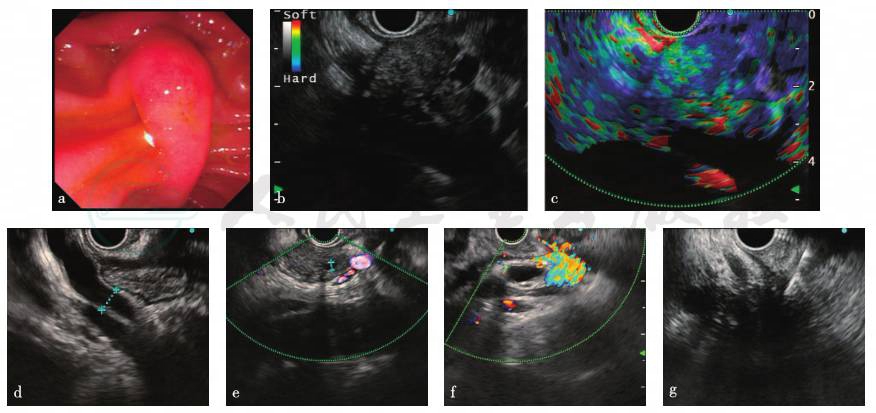

内镜下见十二指肠乳头未见异常;胰腺头部见一低回声病变,边界欠清,横截面大小约3.09cm×2.72cm,多普勒显示少许血流信号,弹性成像为3分;胰腺体部主胰管直径3.0mm;体部及尾部胰腺萎缩;胆总管下段管壁增厚明显,腹腔内可见多发肿大淋巴结(图2)。

图2 EUS-FNA检查

a. 十二指肠乳头;b. 胰腺头部占位;c. 胰腺头部占位弹性成像;d. 主胰管;e. 胆总管;f. 腹腔多发淋巴结;g. FNA穿刺

EUS-FNA病理学检查:胰腺多量血凝块内见少量小肠黏膜;胰腺穿刺涂片,多量红细胞内见极少数异性细胞;十二指肠乳头,小肠组织示慢性炎。免疫组化:十二指肠内淋巴细胞表达IgG(+),IgG4∶IgG<40%,IgG4<50个/HP(图3)。